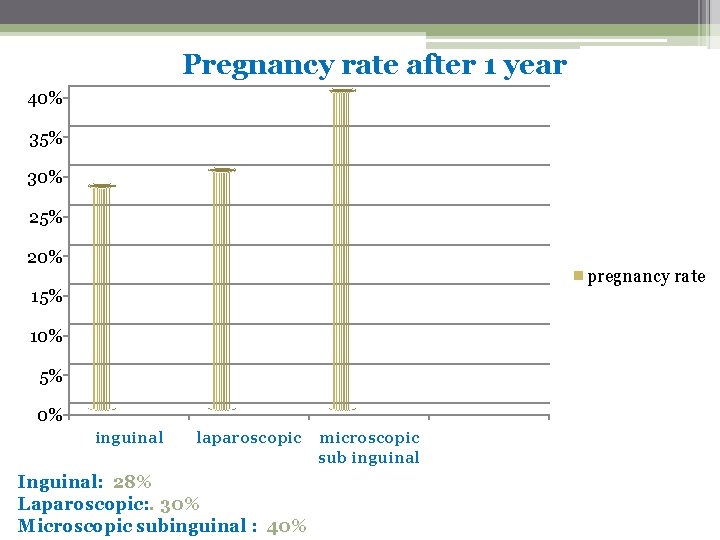

Pregnancy rate after 1 year 40% 35% 30% 25% 20% pregnancy rate 15% 10% 5% 0% inguinal laparoscopic Inguinal: 28% Laparoscopic: . 30% Microscopic subinguinal : 40% microscopic sub inguinal